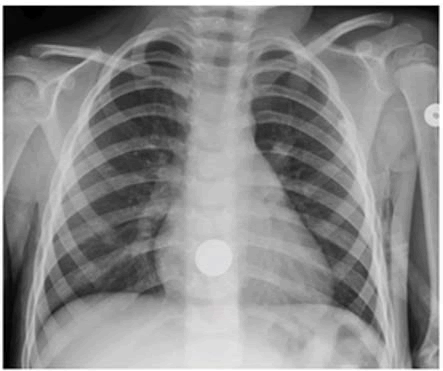

Figure 2 Example of a perceptual error. Ante<oposterior ra diograph of the chest of a 4-year-old boy.The presence of a swallowed coin within the esophagus was missed twice by a skilled pediatric radiologist. The clinical hstory provided did not mention the possibility of a swallowed coin.